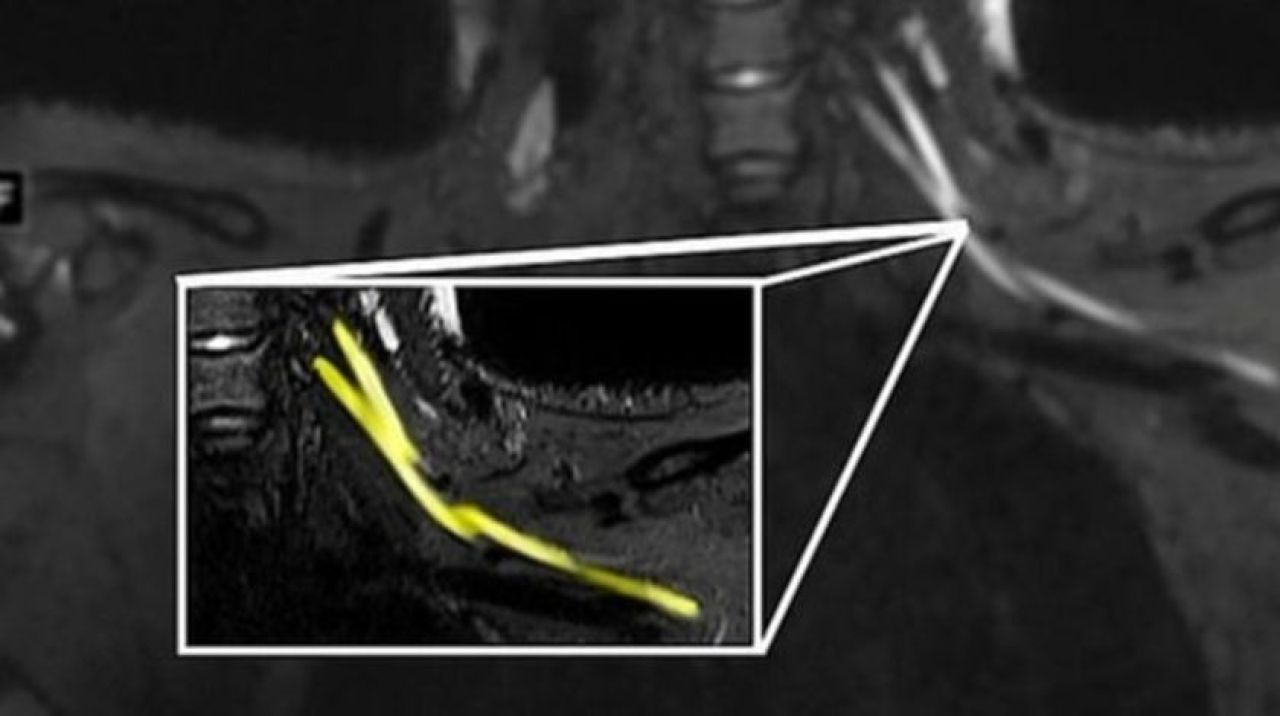

Radiology dergisinde yayımlanan çalışmanın başyazarı Doktorlar Ağrı boynunuzdaki, dirseğinizdeki veya bileğinizdeki sorunlardan kaynaklanıyor olabilir ve bunu anlamanın en iyi yolu MRI veya ultrasondur. Yaptığımız çalışmayla çok küçük sinirleri bile gösteren gelişmiş görüntüleme sunuyoruz. Bu da sorunun nerede olduğunu tespit etmemize, ciddiyetini değerlendirmemize ve buna neyin neden olabileceğini önermemize yardımcı olabilir.

Öte yandan, çalışmanın yazarları gelişmiş ultrason teknolojisinin kolay taşınabilir ve ucuz olduğunu, ayrıca sinir hasarını tespit etmede tomografiden daha iyi olduğunu ifade etti. Araştırmacılar, taramaların doktorların hastaları bir rehabilitasyon uzmanına mı yoksa daha ciddi durumlarda bir cerraha mı sevk edeceklerine dair karar vermelerine yardımcı olacağını aktararak, “Eğer görüntüleme enflamatuar bir tepkiye bağlı sinir hasarı bulursa, hastaya bir nöroloğa görünerek daha iyi hizmet edilebilir. Görüntüleme, hematomdan kaynaklanan sinir hasarını ortaya çıkarırsa, kan sulandırıcı ilaçların derhal ayarlanması gerekir ve hatta hastanın bir cerrahı görmesi gerekebilir” açıklamasını yaptı.